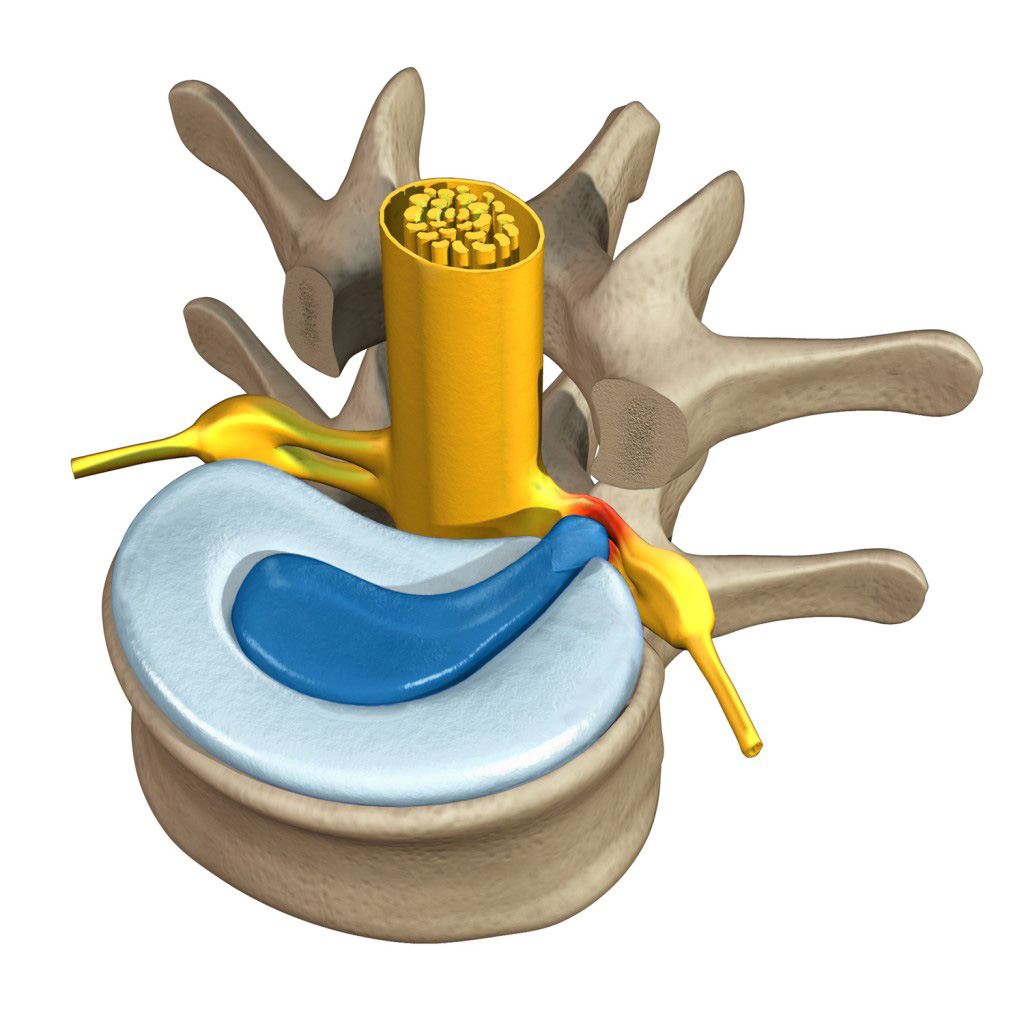

КТ-протрузии дисков: Визуализация и классификация